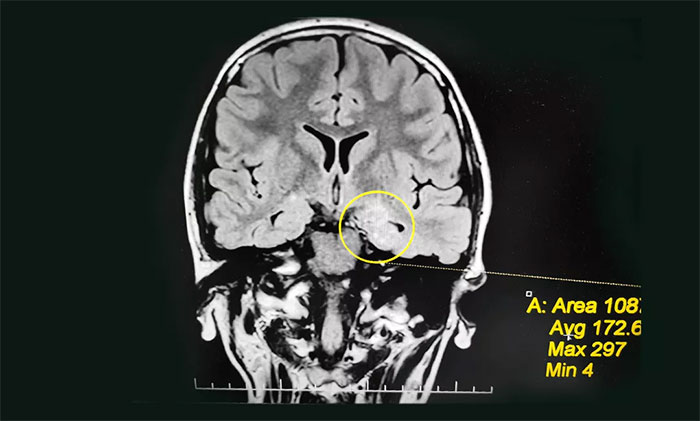

入院后,佳欣接受了一系列檢查:行24小時(shí)長程腦電圖監(jiān)測,提示異常腦電圖;MRI檢查,左側(cè)顳葉海馬區(qū)影像改變,左側(cè)海馬神經(jīng)元受損、局部代謝旺盛,考慮左側(cè)海馬區(qū)軸內(nèi)變性病變,考慮致癲灶可能。

為佳欣診治的楊忠旭教授查看了各項(xiàng)檢查報(bào)告,詳細(xì)了解相關(guān)病情后,考慮佳欣因難產(chǎn)導(dǎo)致大腦缺血、缺氧,而海馬對(duì)這種情況的耐受較差,極易造成其內(nèi)的神經(jīng)細(xì)胞受損,時(shí)間長了就會(huì)發(fā)展成海馬硬化。成年后,近一半以上的病人會(huì)因此患上頑固性癲癇。

楊忠旭教授指出,佳欣的癲癇診斷明確,經(jīng)系統(tǒng)藥物治療無任何改善,確診為難治性癲癇,應(yīng)用現(xiàn)代神經(jīng)影像學(xué)技術(shù)和電生理監(jiān)測技術(shù),能明確引起癲癇發(fā)作的“責(zé)任病變”,且手術(shù)指征明顯,未見明顯手術(shù)禁忌癥。

▲ 通過系列檢查評(píng)估,最終明確患者致癲灶